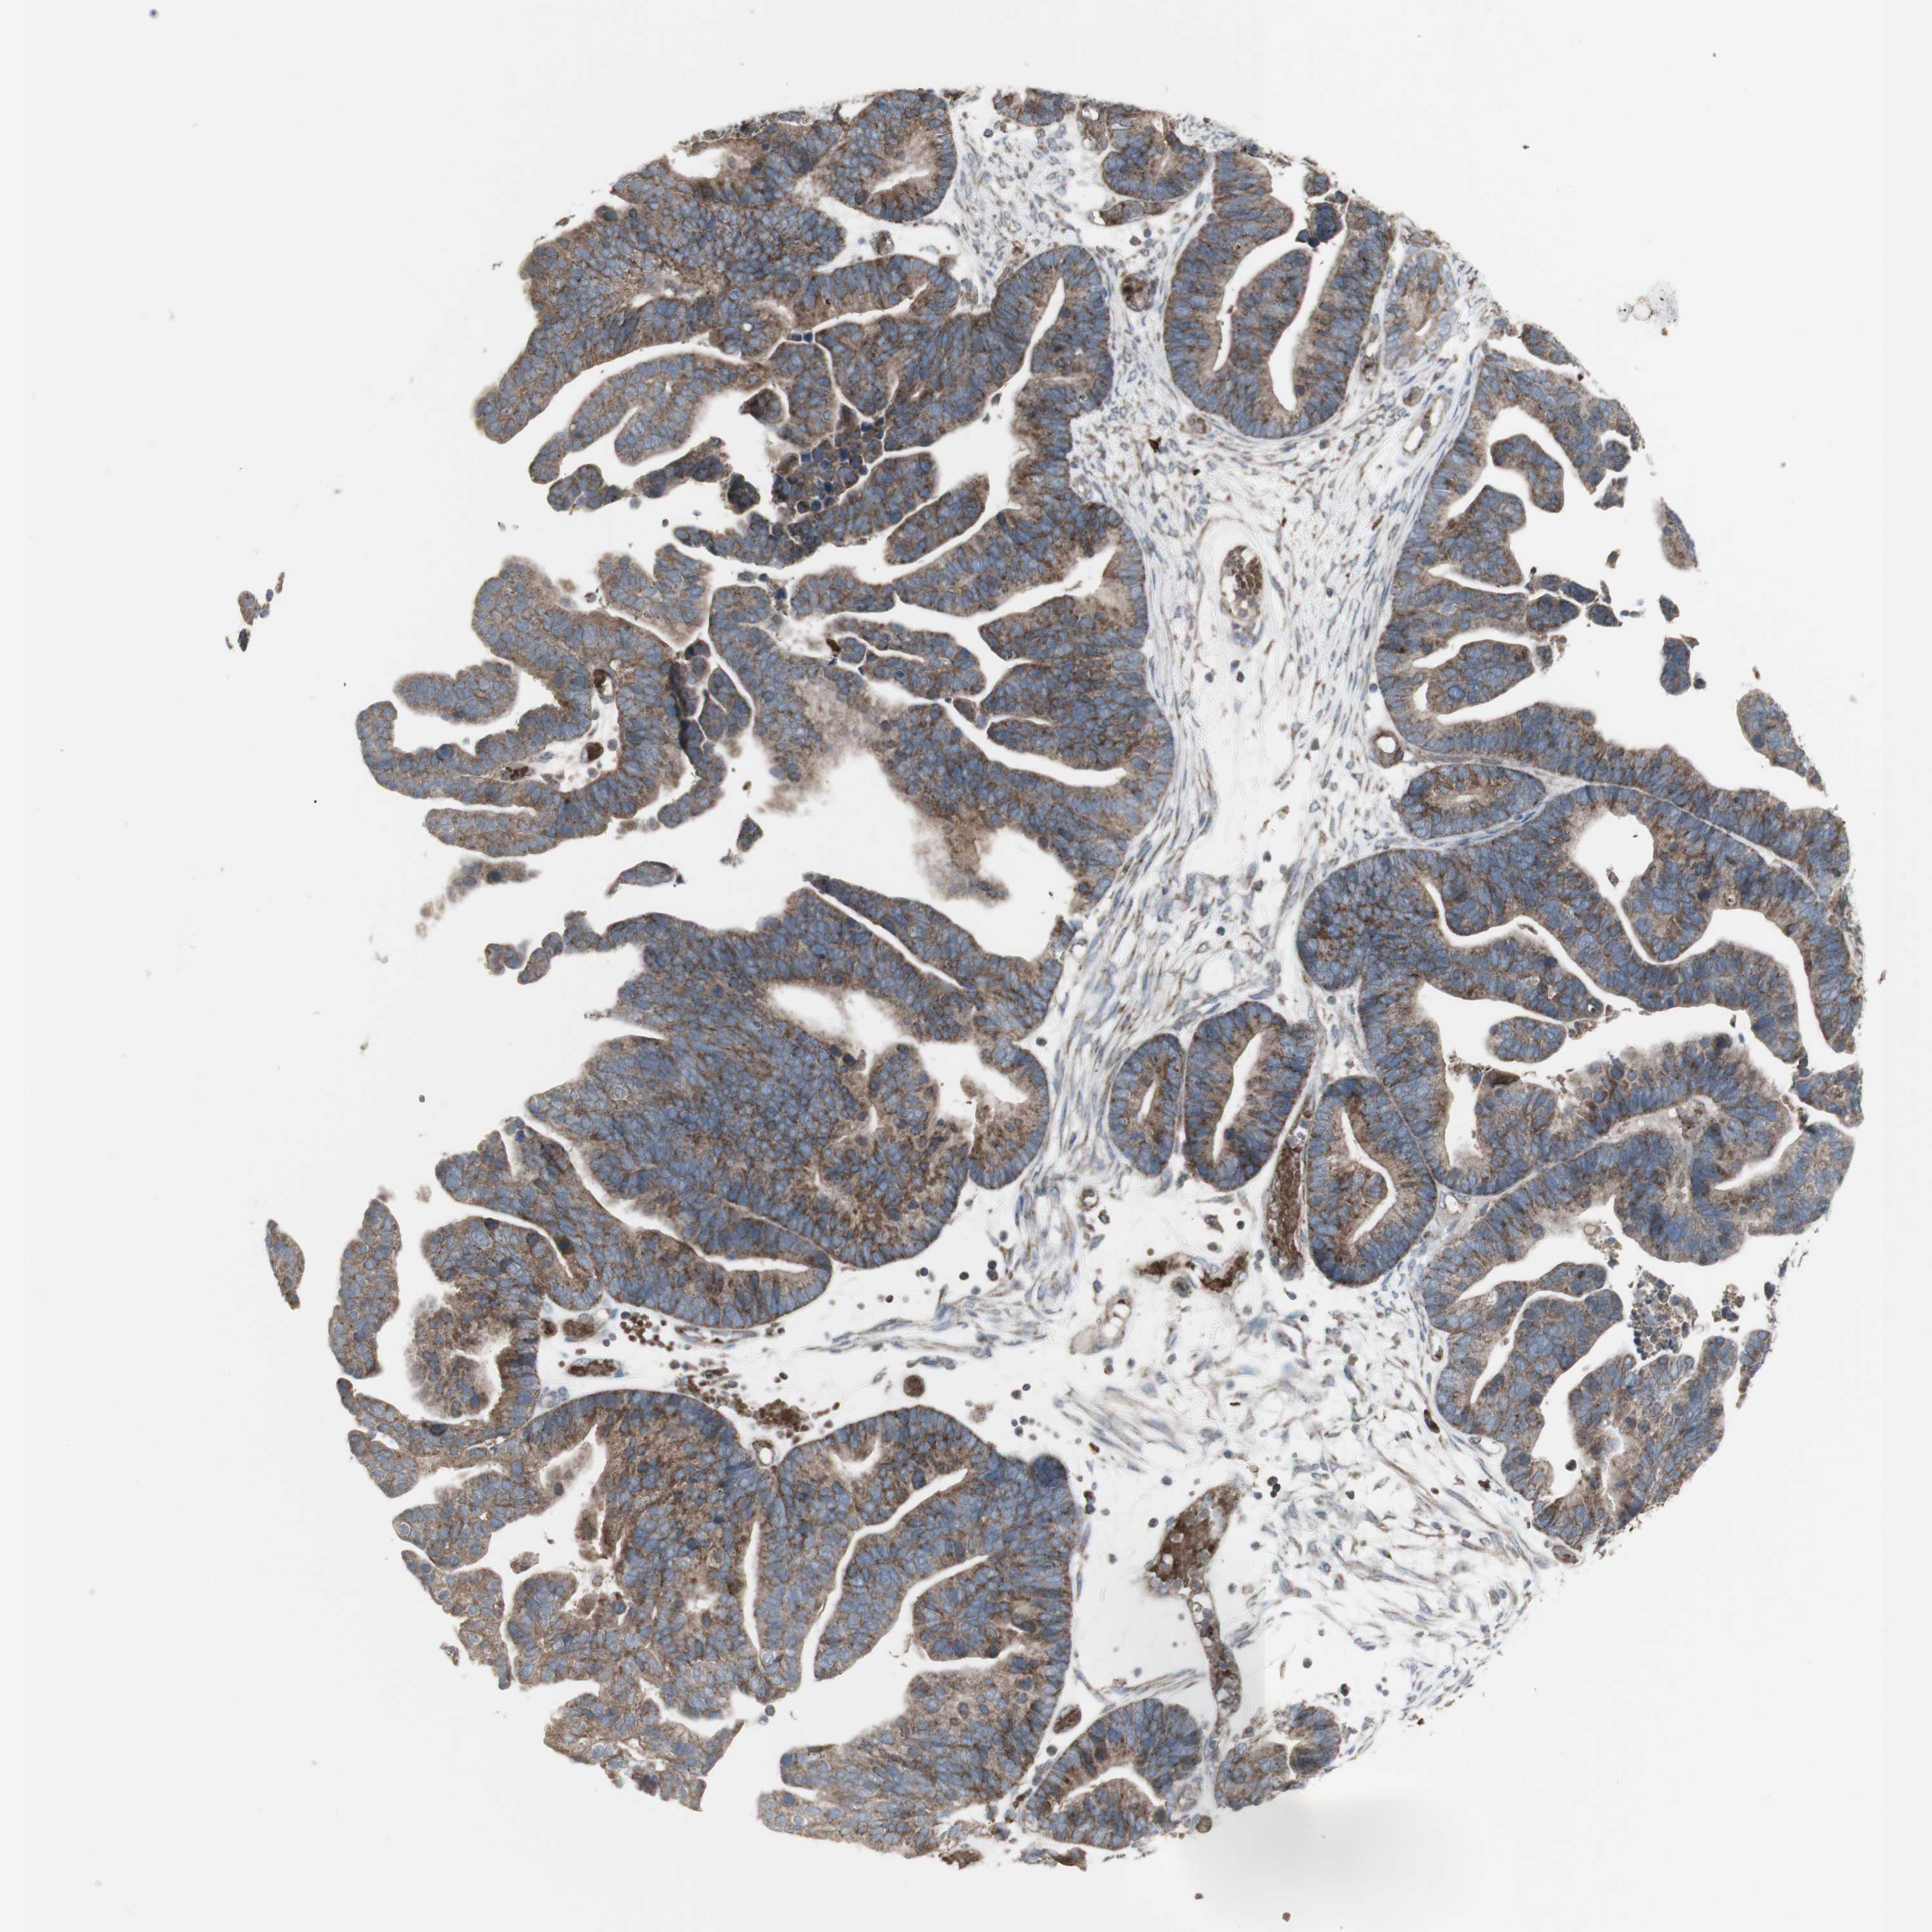

OVARIAN CANCER - Protein expressioni

A mouse-over function shows sample information and annotation data. Click on an image to view it in a full screen mode. Samples can be filtered based on level of antibody staining by selecting one or several of the following categories: high, medium, low and not detected. The assay and annotation is described here.

Note that samples used for immunohistochemistry by the Human Protein Atlas do not correspond to samples in the TCGA dataset.

Antibody stainingi

Antibody staining in the annotated cell types in the current human tissue is reported as not detected, low, medium, or high, based on conventional immunohistochemistry profiling in selected tissues. This score is based on the combination of the staining intensity and fraction of stained cells.

Each image is clickable and will lead to virtual microscopy that enables deeper exploration of all samples and also displays staining intensity scores, fraction scores and subcellular localization as well as patient and tissue information for each sample.

Antibody HPA001844

Cystadenocarcinoma, serous, NOS